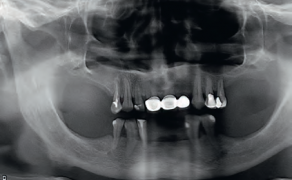

- Przypadek 1: Pacjent ogólnie zdrowy, lat 32, zgłosił się w celu wykonania badania stomatologicznego. Na wykonanym pantomogramie uwidoczniono rozległą torbiel okolicy zębów 45-47.

- Przypadek 2: Pacjent zgłosił się do Poradni w celu sanacji jamy ustnej. Badanie radiologiczne uwidoczniło zmianę o charakterze torbieli okolicy zęba 36. Stan po ekstrakcji zęba 37 rok wcześniej.

Streszczenie: W pracy przedstawiono dwa przypadki torbieli żuchwy o średnicy około 3 cm. Zastosowano leczenie jednoetapowe, podczas którego usunięto zmiany w całości wraz z przyczyną zębopochodną. Leczenie poprzez wyłuszczenie torbieli jest metodą z wyboru ze względu na zminimalizowanie ryzyka transformacji nowotworowej, możliwość oceny całego preparatu przez histopatologa oraz z powodu generowania najmniejszych niedogodności dla pacjenta. Diagnostyka z wykorzystaniem stożkowej tomografii komputerowej (CBCT) pozwoliła na ocenę wrażliwych struktur anatomicznych i zaplanowanie postępowania tak, aby zredukować ewentualne powikłania.

Summary: This paper presents two cases of mandible cysts with the diameter of approximately 3 cm. One-stage treatment was performed, during which the lesion was removed along with the affected teeth. Enucleation is a method of choice because it minimises the risk of cancer transformation, enables histopathological evaluation of the entire lesion and is the most comfortable for a patient. Diagnosis with the [...]